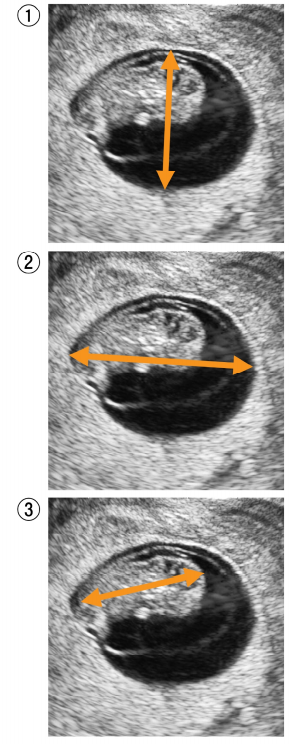

26 頸部造影 CT別冊No. 3を別に示す。 このスライスレベルで確認できないのはどれか。 (A)喉 頭 (B) 甲状腺 (C)外頸静脈 (D) 総頸動脈 (E)胸鎖乳突筋